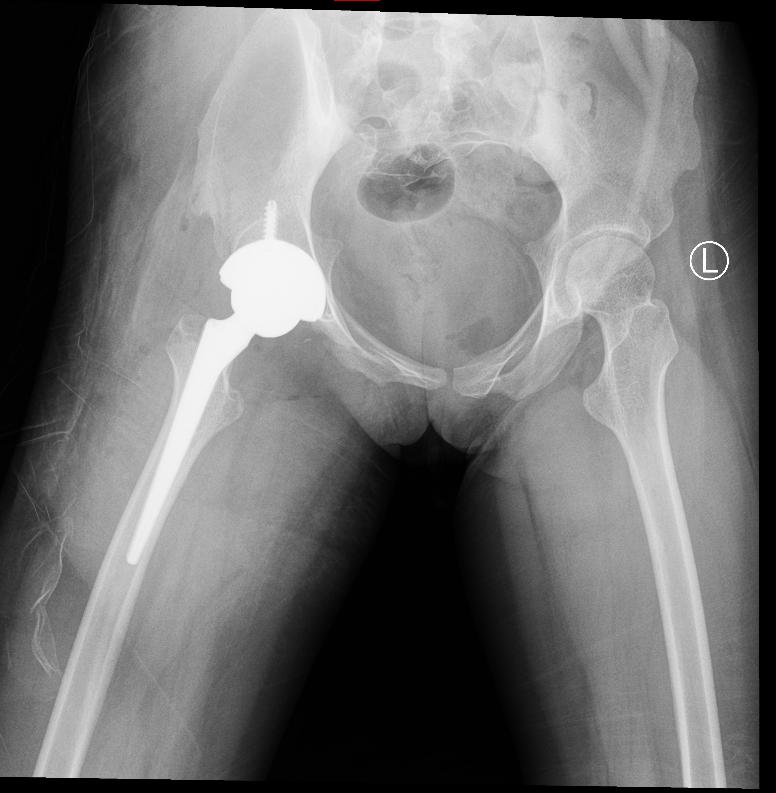

据了解,小肖今年18岁,曾因脊髓瘤多次在外院接受手术,并患有双侧马蹄足、小便失禁等后遗症,需长期携带尿管生活,因右髋关节发育不良在我院治疗。据患者反映,右侧髋关节疼痛难忍,吃止疼药已无法减缓疼痛。考虑到患者病情比较复杂,陈柯主任和他的团队根据患者病史、影像资料、体格检查等信息制定了详细的诊疗方案,于2024年7月15日给患者做了右侧全髋关节置换术,现术后恢复良好,右髋关节疼痛明显缓解,关节功能基本恢复。

陈柯主任团队还邀请足踝外科主诊医师穆世民和史可钊医师给予会诊并给出相关治疗方案建议,待患者髋关节置换术后恢复稳定后择期来我院行双侧足踝融合术,进一步改善患者双下肢功能状态,提升患者生活质量。